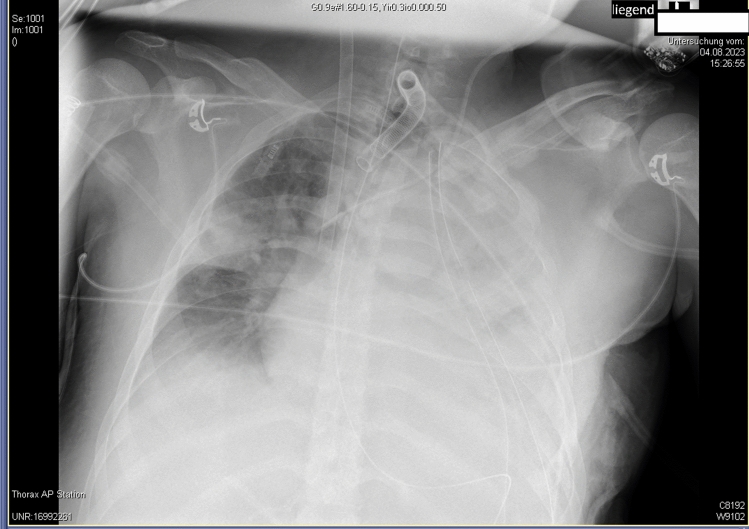

The use of veno-venous extracorporeal membrane oxygenation (VV-ECMO) has become increasingly prevalent, particularly in respiratory disease pandemics such as H1N1-influenza and SARS-CoV-2. This surge has emphasized the importance of clear therapy recommendations, improved accessibility to ECMO technology, established ECMO teams, and structured networks to ensure access to specialized care throughout the course of the disease for patients with severe ARDS. Although the initiation criteria for VV-ECMO are well defined, treatment strategies while on ECMO regarding e.g., ventilator management or ECMO weaning strategies remain variable and with lack of consensus. NAVA (Neurally Adjusted Ventilatory Assist), as an assisted mechanical ventilation modality, offers real-time electromyographic feedback, which has been shown to enhance prolonged weaning processes from mechanical ventilation. We present a case of penetrating thoracic trauma complicated by ARDS, successfully managed with VV-ECMO. NAVA was employed to monitor and facilitate ECMO. This approach integrates ECMO weaning with ventilation settings, considering both gas exchange lung function, such as carbon dioxide removal, and respiratory mechanics in the form of neuromuscular coupling. This is a new approach to VV-ECMO weaning. More research is planned to validate the efficacy of this method in conjunction with additional parameters, such as diaphragm activity evaluated sonographically in a randomized design. This case underscores the potential of NAVA in VV-ECMO weaning, offering a promising avenue for optimizing patient care and outcomes.